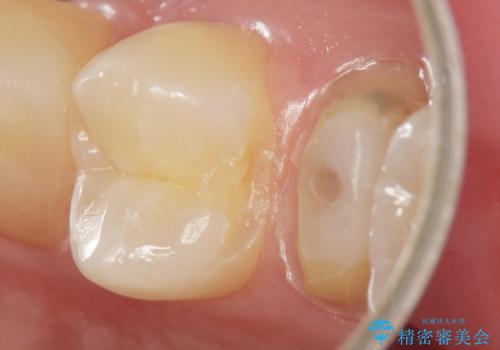

精査したところ、左上の小臼歯(左上5)は被せ物がないまま放置していたことにより、両隣の歯が寄ってきてスペースが少なくなり、また隣の歯(左上4)も虫歯になっていました。

隣の歯の虫歯治療(保険内のレジン充填)後、セラミッククラウンによる補綴を行いました。

以前つけた被せ物は1週間でとれてしまったそうで、歯ぎしりのご自覚もあることから、咬み合わせの調整を丁寧に行いました。

仮歯およびクラウンの仮付け期間を設け、はずれにくいことや咬み合わせに問題がないことを確認した上で本付けを行いました。